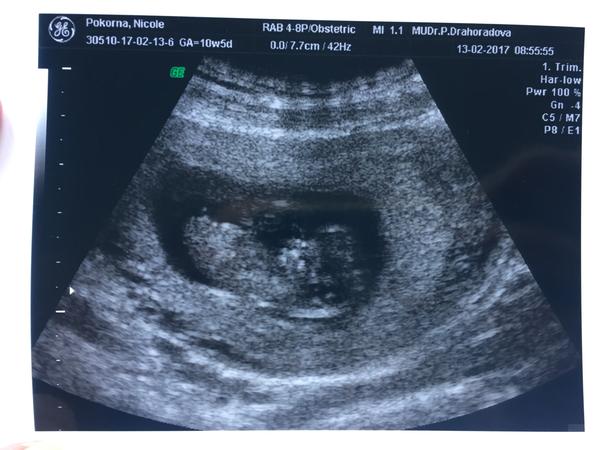

@marketa11112 jestli se doktorka přiklání k holčičce, tak jsem přesvědčená, že to určovala z jiného pohledu. Něco by řekla fotka ze spodu zadečku, jako když bys udělala fotku sedícího člověka na skleněné židli z pod židle - to je popis...🙂

@marketa11112 opravdu to vypada na slecnu 👍 nase mala mela dost velky vybezek,ale smeroval dolu a rekli kluk no a od 17tt holka 3x potvrdili tak to snad i zustane 😔